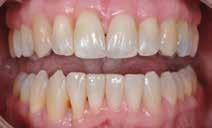

I samråd med patienten og egen tandlæge* afstemmes forventningerne, inden der bestilles refinement alignere. Nivelleringen af alle tænder i tandbuerne, smilelinje og -kurve samt den bukko-lingvale position af incisiverne foretages og efterfølges af retainers lingvalt på over- og underkæbeincisiver (Fig. 3 A-D). Hele behandlingen udføres under løbende kommunikation med patient og egen tandlæge*, der udfører den efterfølgende rekonstruktion med direkte plast (Fig. 4 A-D). Behandlingsvarigheden har været to år og to måneder, hvor ortodontien har forløbet over 21 måneder. Der har været anvendt et første sæt på 66 alignere samt yderligere to sæt med ni refinement alignere. Tandblegning og direkte plastrekonstruktion er udført af egen tandlæge* (Fig. 5 A-F).

Fig. 5. A, B. Smil og kæbeforhold før og efter. Et bredere smil med korrektion af de laterale mørke rum. C-F. Harmonisk hældning af overkæbe- og underkæbeincisiver, rekonstruktion af den tabte tandsubstans efter nivellering af gingivaniveau og optimal bukko-lingval placering til direkte plastbehandling.

5. A, B. Smile and jaw relationships before and after. A wider smile with correction of the lateral dark spaces. C-F. Harmonious inclination of the upper and lower jaw incisors, reconstruction of the lost tooth substance after leveling the gingival level, and optimal bucco-lingual positioning for direct plastic treatment.